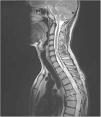

Posttraumatic syringomyelia (PTS) is a well-reported phenomenon that usually takes place in the long-term course of patients following spinal cord injury. Different surgical procedures have been described: spinal cordectomy is usually a last option technique, but might be an excellent choice in patients with severe spinal cord injuries.

We present a young patient with complete spinal cord injury after spine trauma, who developed posttraumatic syringomyelia with progressive motor deterioration twelve years after fixation. We performed a novel surgical technique (myelopexy) with excellent resolution of syringomyelia, sparing the negative implications of complete cord transection. Some artistic illustrations made by one of the corresponding authors are included, to better understanding of operative details.